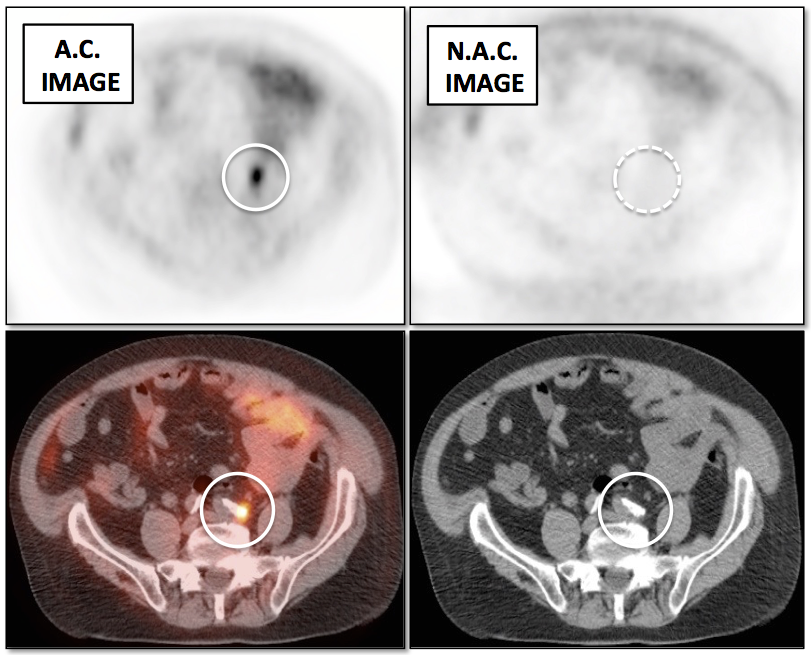

Value of Non-Attenuation Corrected (NAC) Images

Resolving Attenuation Correction Artifacts:

The CT images obtained during an exam are not only used for “anatomic” interpretation. They are also used for “attenuation correction” (AC) of the PET images, generating the much more useful AC PET images used for interpretation.

Unfortunately, attenuation correction of PET images can result in falsely elevated metabolic activity in regions of high CT density (e.g. metallic devices, oral contrast, calcification).

In such cases, these areas must be reviewed on the NAC (non-attenuation correction) images. If these regions are not also hypermetabolic on the NAC images, then their apparent increased FDG-uptake on the AC images is artefactual.

This phenomenon is almost exclusively seen with older PET/CT scanners, as most modern scanners utilize newer algorithms that do not “over-correct” in these areas of increased density.